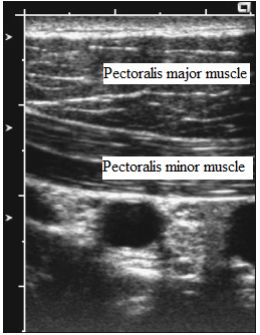

10. 圖所示是臂神經叢(Brachial plexus)阻斷的哪一個Level?

(A) Interscalene (B) Supraclavicular (C) Infraclavicular (D) Axillary